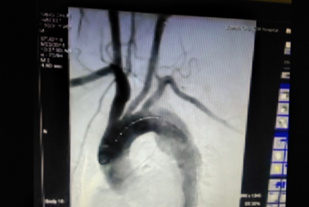

術(shù)前CT檢查(顯示為主動(dòng)脈夾層)